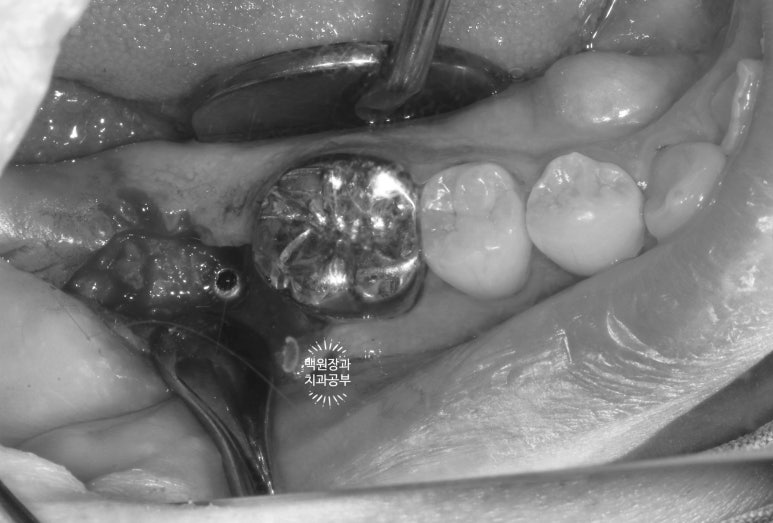

그래도 아쉬우니.. 충치라고 생각되는 부위를 제거해봅니다.

머리가 부러진 오른쪽 아래 어금니...

충치라고 생각되는 부위를 조심조심 제거해보았습니다.

보시면 안에 분홍색으로 동그랗게 보이시는게 있죠?? 옛날에 신경치료 때 사용했던 재료에요!

GP cone 입니다.

그 정도로 제거했는데도 여전히 까만색의 치아만 남아있네요...

이 치아는 뿌리 내부까지 썩었다고 판단되어 뽑기로 결정하였습니다.

이차 충치가 너~무 심해져서 뿌리 속까지 썩어버리면 그 치아는 포기해야합니다.